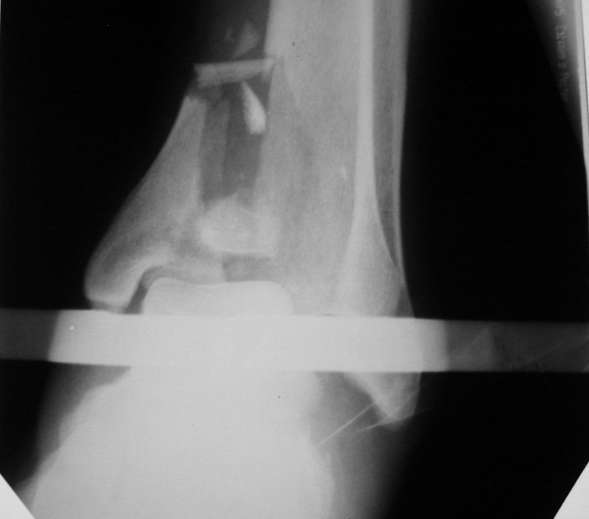

Было решено, уже по ходу операции, выполнить артродез болтом-стяжкой, тем самым компрессируя резецированные суставные поверхности и смещая стопу латерально, дабы нивелировать варусную деформацию и восстанавливая тем самым опорную ось всей конечности.

Вчера (прошло около 8 месяцев)больной обратился ко мне в очередной раз с жалобами на боли умеренно-жгучего характера в области выстояния концов болта-стяжки. На момент осмотра:укорочение левой нижней конечности на 1,5 см; гипотрофия медиальной группы мышц голени и четырехглавой мышцы бедра; передвигается без дополнительной опоры в ортопедической обуви на растояние до 5 км; работает приемщиком цветных металлов (приходится перетаскивать грузы). Нарентгенограмме, насколько это можно видеть, костного блока сформировать не удалось, но движений в голеностопном суставе нет - ни активных, ни пассивных. Послеоперационные рубцы б/о; свищей и нагноения не было. Активно больногонаблюдать не приходилось, т.к. проживает в другом городе.

ЗЫ: Прошу прощения за очень низкое качество представленных ренгенограмм. Буду очень признателен за комментарии.